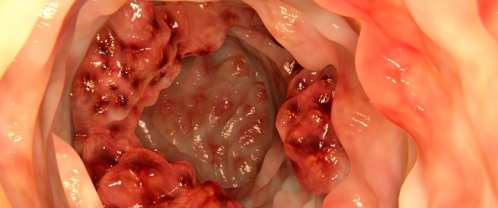

احمي نفسك من سرطان القولون باتباع هذه النصائح